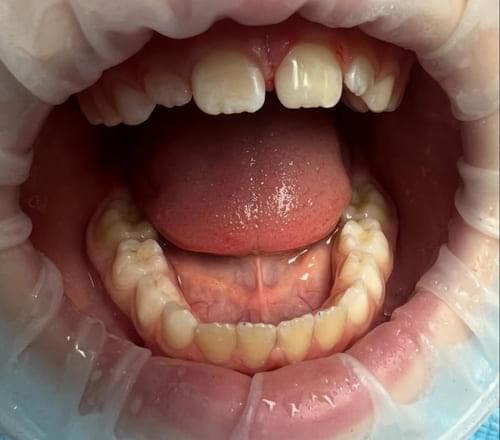

Дівчинка 7 років, перше вересня, гойдалка… Вивих постійного зуба: якщо в такій ситуації зволікати, дитина може втрати постійний зуб назавжди. Батькам порекомендували нас і пацієнти одразу приїхали. Через складність і травматичність процедур вирішено проводити лікування в анестезіологічному супроводі. Зуб поставлений на місце (репонований), проведена хірургічна обробка і ушивання рани губи. Останнє фото через рік після травми: зуб на місці і корінь продовжує розвиватись, губа повністю загоїлась